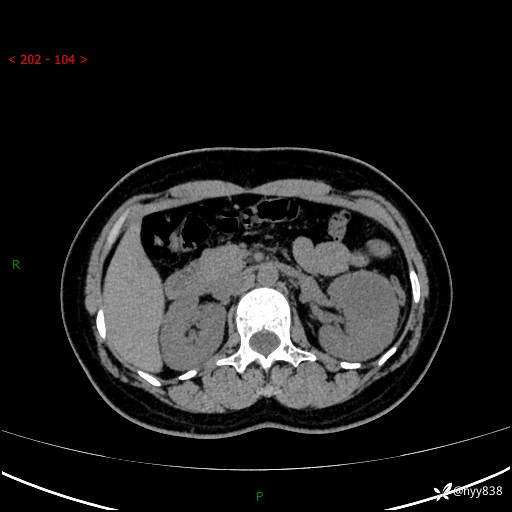

现病史:患者于1周前因左侧腰腹部间断胀痛不适,无恶心呕吐,无明显肉眼血尿,无畏寒发热,无尿频尿急,起病初,患者来我院就诊,查CT提示左肾低密度影,外周血提示:白细胞11.25*10^9/L.行抗感染治疗后未见明显好转,06-18泌尿系增强CT提示左肾类圆形低密度占位(脓肿?肿瘤?),大小:4.0*3.2cm,为求进一步治疗,门诊以“左肾占位”收住我科。 起病以来,患者精神佳,饮食、睡眠良好,大小便正常,体力体重无明显变化。

双肾CT平扫+增强